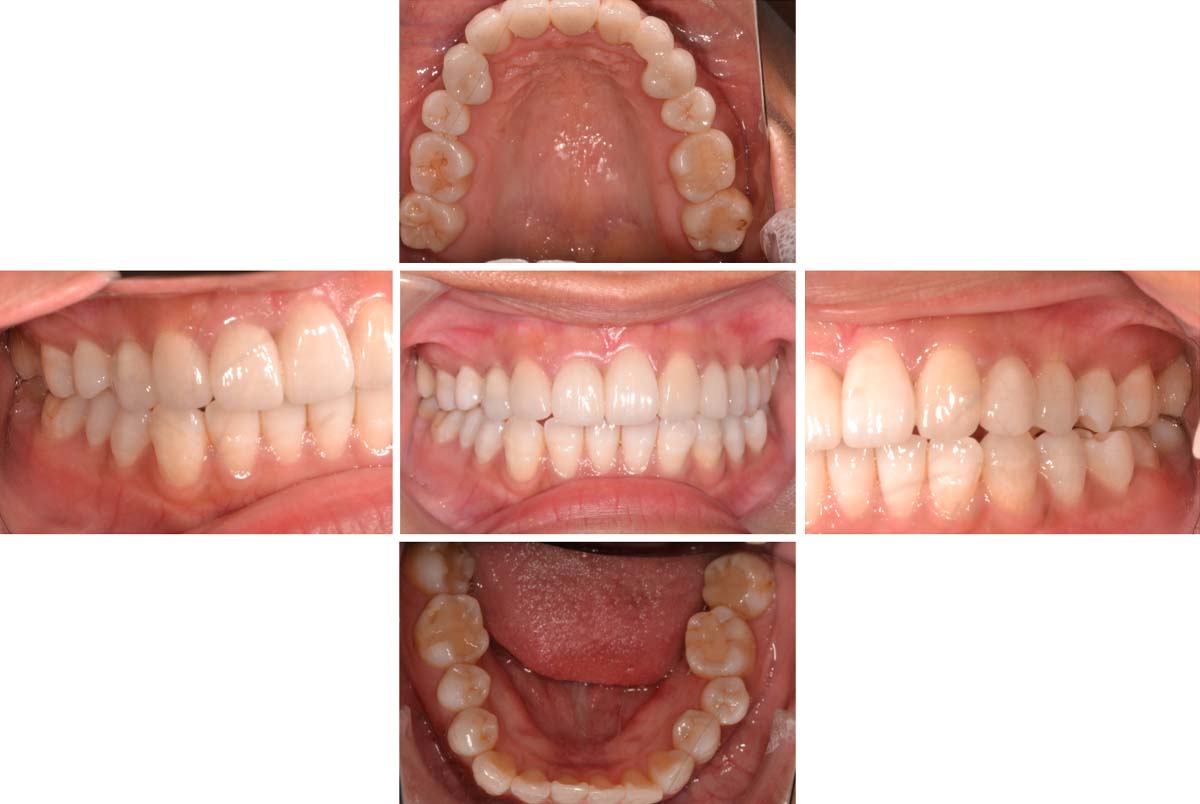

| 術後 |

![]() |

年齢:36歳

主訴:歯が痛い

初診時の診断と治療方針

初診時の口腔内写真です。主訴の歯の痛みは、斜めに生え噛む面が虫歯になっている右下親知らずであることが分かります。また、その他の部位にも多くの修復物や歯列の乱配を認め、う蝕と歯周病共にリスクが高いことが考えられます。

さらに、歯列の乱配だけでなく傾斜、はまり込みを認めます。 X線写真では全顎的な軽度の歯周病の進行、左下には歯根の著しい吸収を認める乳歯も残っています。引き続き医療面接、う蝕や歯周病の詳しい検査を進め、治療方針についてカウンセリングを行った結果、患者様は顎関節の不調も感じており、インプラントや矯正を含めた全顎的な咬合治療を行っていくことになりました。